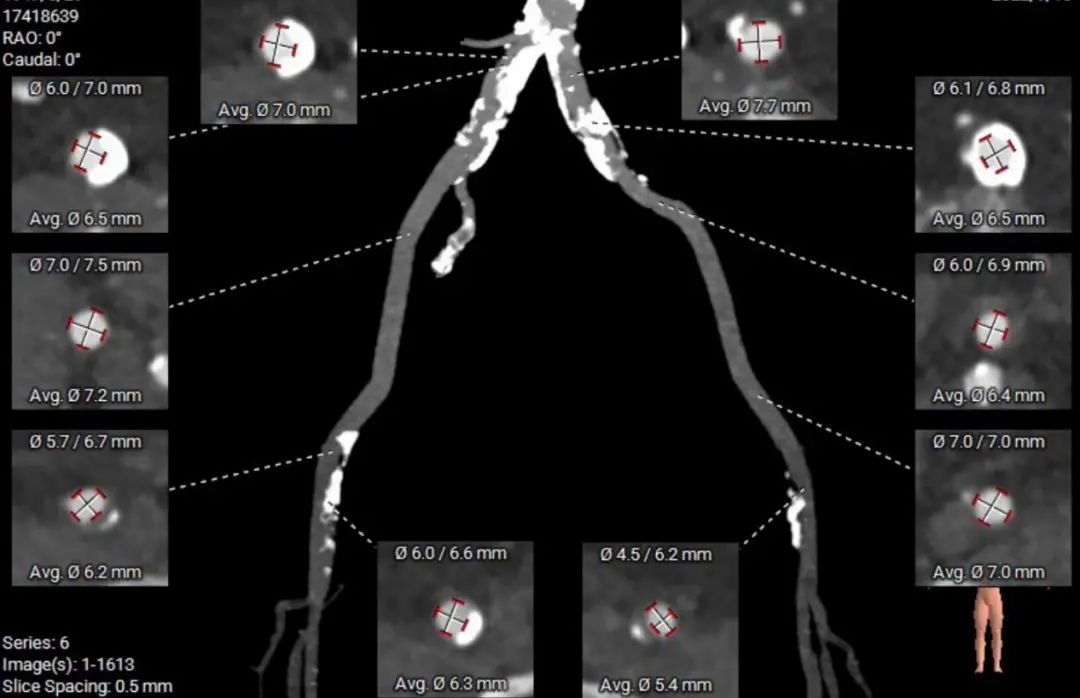

外周血管及主动脉弓解剖

股动脉入路无迂曲,分叉高度可。髂总、腹主钙化分布。左侧血管平均最小内径6.0mm, 右侧血管平均最小内径6.0mm。

建议右侧股动脉为主入路,穿刺点附近少量钙化分布,建议避开钙化穿刺。